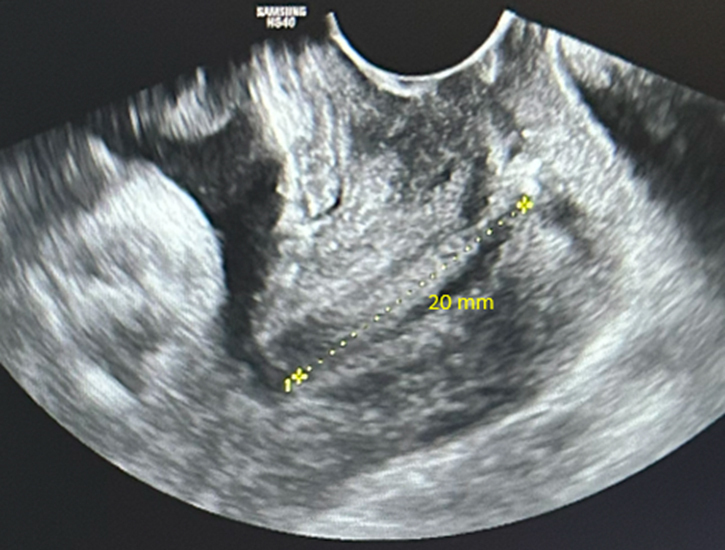

Une menace d’accouchement prématuré se définit comme des contractions utérines régulières et douloureuses (ici 5 par dix minutes visibles à la tocométrie) et un col raccourci ou modifié cliniquement (ici mesuré à 20 mm à l’échographie endovaginale). Un col non modifié est dit long, tonique, postérieur, fermé avec une présentation fœtale non sollicitante.

Concernant l’échographie endovaginale.